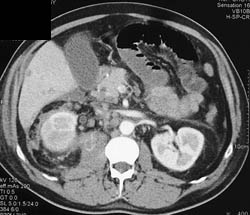

Liver Metastases